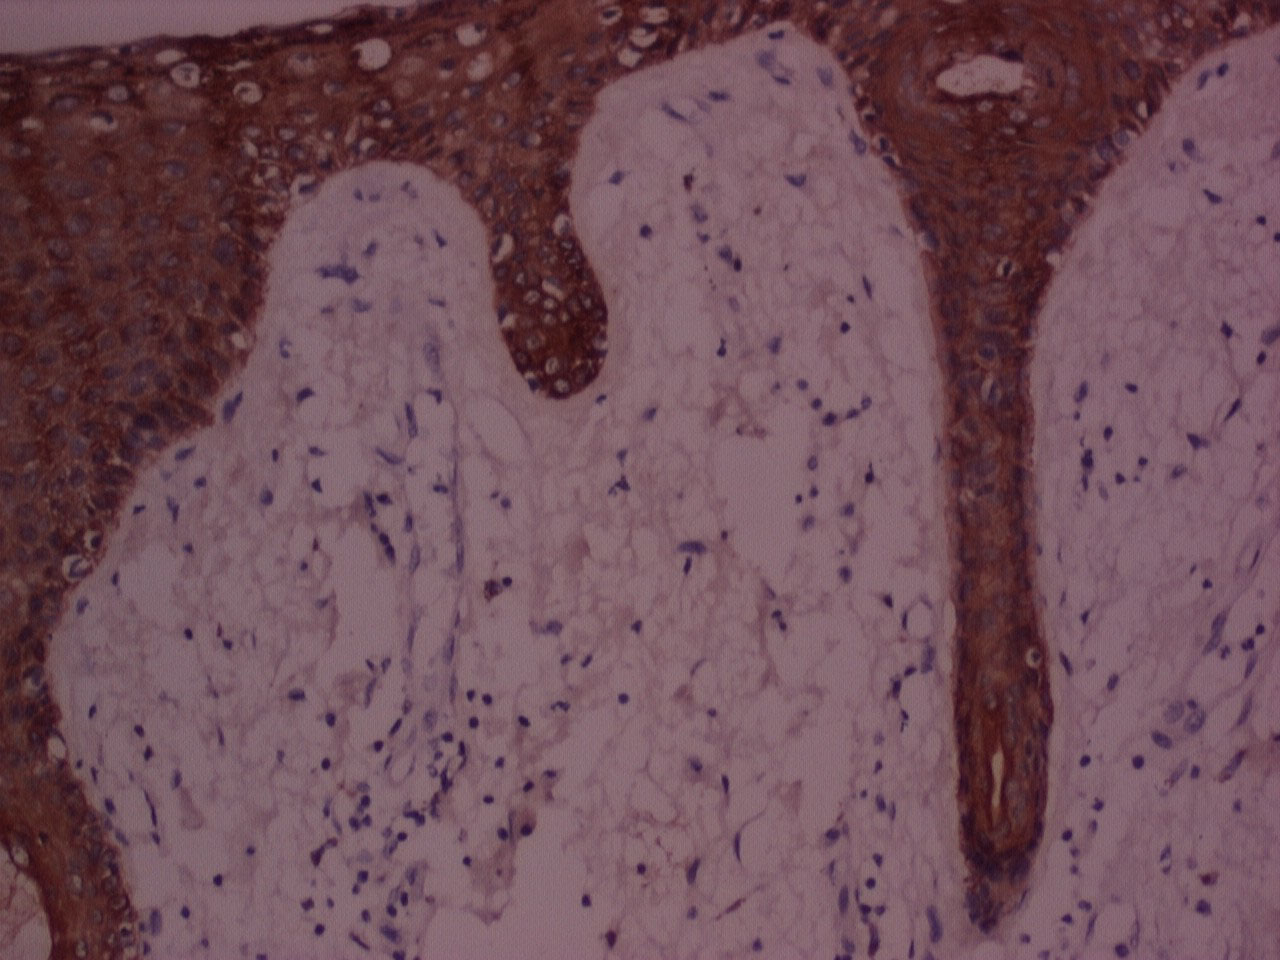

The majority of the samples processed with n-Heptane showed weak to moderate IHC staining for cytokeratin and vimentin (Figure 5, Figure 6, Figure 7, Figure 8 and Figure 9) with none of the sections devoid of staining.

Figure 6: IHC stained photomicrograph of section showing cytokeratin positivity, processed with Xylene, 10x. View Figure 6